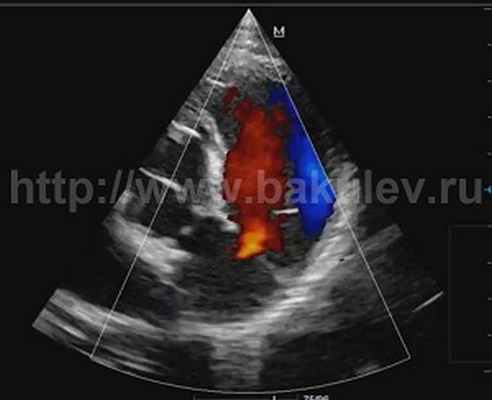

У 30% с умеренной и выраженной регургитацией визуализировались две струи (рис. 1). При выраженной регургитации плотность струи была выше, чем при

Выраженная легочная регургитация, две струи.

Цветное допплеровское картирование потока - наиболее широко используемый метод для идентификации ЛР, определения размера и пространственной ориентации потока. Площадь потока, особенно, индексированная к поверхности тела, хорошо коррелирует с тяжестью ЛР. Более точным методом оценки степени ЛР считается измерение ширины vena contracta струи. Некоторые исследователи использовали ширину потока ЛР также для оценки легочного гомографта, но стандарты для ширины vena contracta при ЛР не были установлены [4].